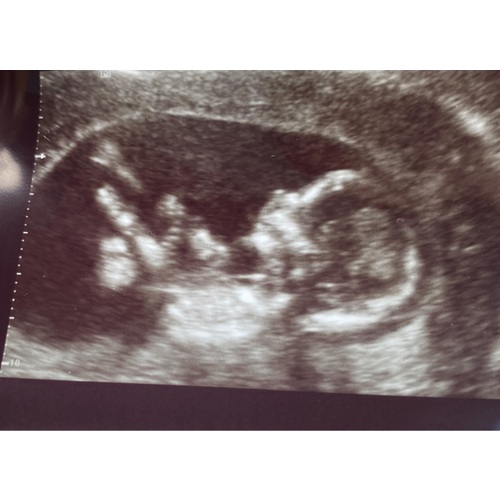

Ik ben bijna 13 weken zwanger. Het is mijn eerste zwangerschap en ben 38 jaar. 2 dagen geleden had ik vers rood bloed bij het afvegen. Ik was zo bang dat het mis zou zijn. Mijn vriend was niet thuis en ben snel met mijn moeder naar de verloskundige geweest. Ik was heel erg in paniek en heb verschrikkelijk gehuild (ook hormonen denk ik) je denkt dat je veilig zit na 12 weken en dan gaat het misschien toch mis. Verloskundige heeft me snel gerustgesteld en laten zien dat de kleine het nog steeds goed maakt.